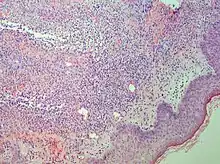

| Sweet syndrome lesions with the classical form of the dermatosis. | |

Studies show a moderate neutrophilia (less than 50%), elevated ESR (greater than 30 mm/h) (90%), and a slight increase in alkaline phosphatase (83%). Skin biopsy shows a papillary and mid-dermal mixed infiltrate of polymorphonuclear leukocytes with nuclear fragmentation and histiocytic cells. The infiltrate is predominantly perivascular with endothelial-cell swelling in some vessels, but vasculitic changes (blood clots; deposition of fibrin, complement, or immunoglobulins within the vessel walls; red blood cell extravasation;inflammatory infiltration of vascular walls) are absent in early lesions.Perivasculitis occurs secondarily, because of cytokines released by the lesional neutrophils. True transmural vasculitis is not an expected finding histopathologically in SS.